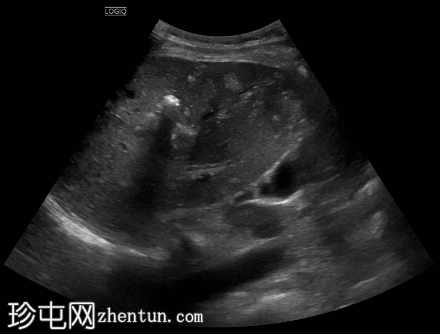

超声检查

5.png

纵向

位于肝段VIII中心的异质性肿块,其特征为不规则的高回声边缘、内部粗钙化以及中心低回声至无回声的液-液平面。还可见多个较小、边界清晰的高回声卫星灶。